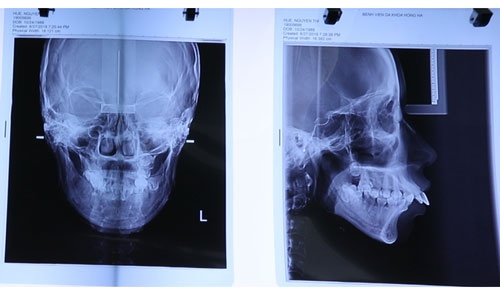

Nguyễn Thị Huê được thăm khám chuyên sâu, chụp xương cùng máy CT SCanner, bác sĩ chuyên khoa chỉnh hình hàm mặt nhận định đây là trường hợp KHÓ, PHỨC TẠP.

Thông qua hình ảnh chụp xương hàm mặt, bác sĩ có thể khẳng định phần tiền hàm trên hình thành quá phát, đẩy ra ngoài tới 3cm.

Do vậy, khớp cắn hai hàm lệch hoàn toàn ảnh hưởng trực tiếp tới sự cân đối khuôn mặt và chức năng ăn nhai của bạn Nguyễn Thị Huê.

Không chỉ khung xương hàm mà ngay phần trục răng cũng bị đẩy cong ngả ra phía trước. Điều này khiến phần miệng của Huê không thể đóng chặt lại.

Có thể thấy rõ, vùng môi trên luôn bị hở do toàn bộ thân răng bị lộ nằm phía ngoài khung hàm. Tình trạng này không thể chỉ đơn giản can thiệp niềng răng như các trường hợp vẩu thông thường.

Vùng xương cằm thiếu hụt, ngắn lẹm so với tổng thể chiều dài khuôn mặt nên khi nhìn trực diện càng lộ rõ khuyết điểm hàm hô vẩu nặng.

Huê chụp xương bằng công nghệ 4.0 đánh giá tình trạng mức độ khuyết điểm hàm và răng